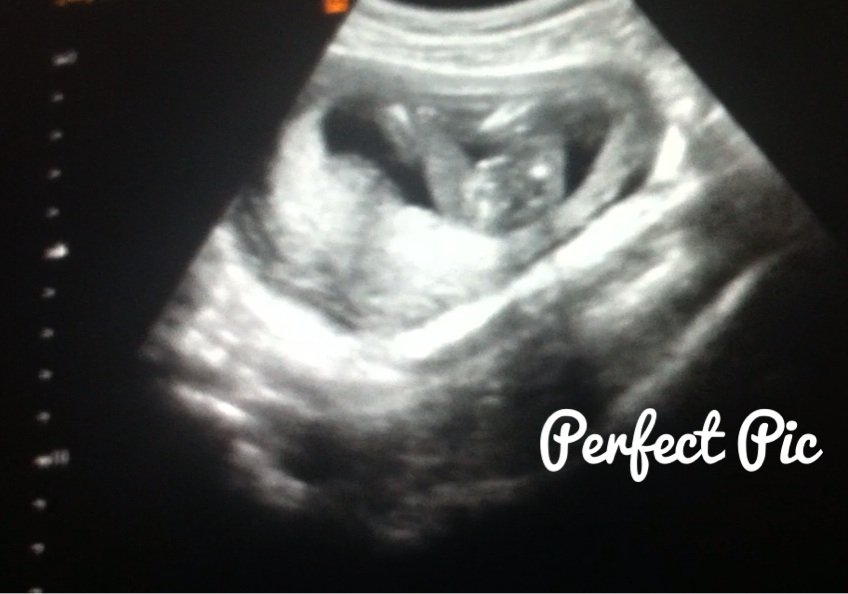

Attachment 19527Attachment 19528At my NT scan at 13 weeks (baby measured 14 weeks 1 day) the tech said if she had to bet she would say it is a girl. Yesterday I had a scan at 16 weeks(not sure where baby is measuring) with my ob he said he's not an expert but that he agrees with the tech that baby is a girl and that we can tell family just not announce on facebook(not a problem for me :) ). I'm still nervous that our little girl is actually a boy that's why I would love some more opinions/guesses from you all. Thanks!